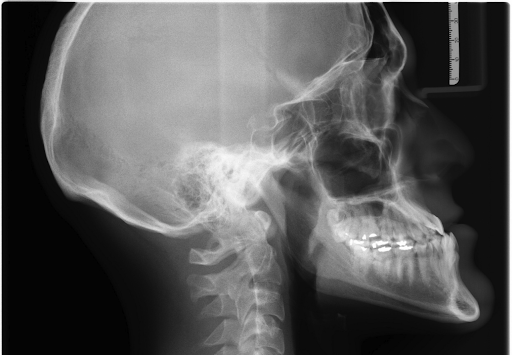

X-rays used to use film to capture an image. But today, more and more dental offices use digital x-rays. These use digital sensors to capture images, allowing for immediate viewing and analysis on a computer screen. Digital X-rays offer faster processing and the ability to manipulate the image.